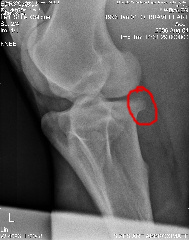

Posted on Thursday, Sep 21, 2006 - 2:45 pm: Oh thank you Mary!I know all about needing patience, I need to find some myself! Here is a pic of his stifle, I've circled in red where I think the vet said the changes were in the stifle: The hock spur is on the front/middle of the lower tarsus, small, and in a good place, if there is such a thing. Both stifle and hock changes are on the left hind. I checked Brave yesterday and I believe he was 1 out of 10, his stifle looked funny, sliding out behind him. My next step is to rehab his stifle to get him muscled up, if that doesn't work, I will be pursuing other avenues... so I truly appreciate your input Anything that stops djd is worth any amount of money, as far as I'm concerned Wishing you luck on this!! I hope this helps your boy